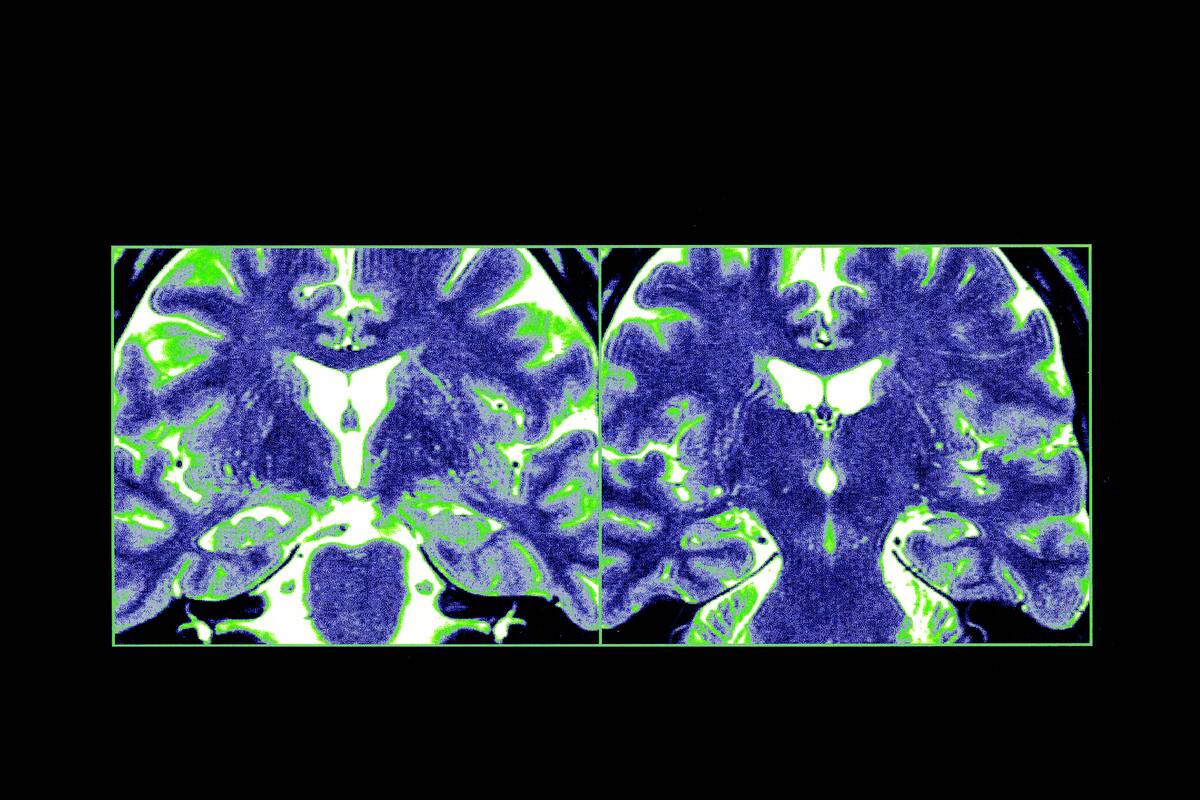

Factors like attention and focus play a crucial role here. The hippocampus, a small seahorse-shaped region, acts as a critical hub in this process, helping to transfer new information into long-term memory. Without it, our ability to form new memories would be severely impaired.

The hippocampus is a crucial player in the storage and retrieval of memories. It acts like a librarian, organizing and categorizing information so it can be accessed later. This brain region is particularly important for the formation of new memories and connecting them to existing ones.

Damage to the hippocampus can lead to difficulties in forming new memories, illustrating its essential role in our ability to retain information over time.